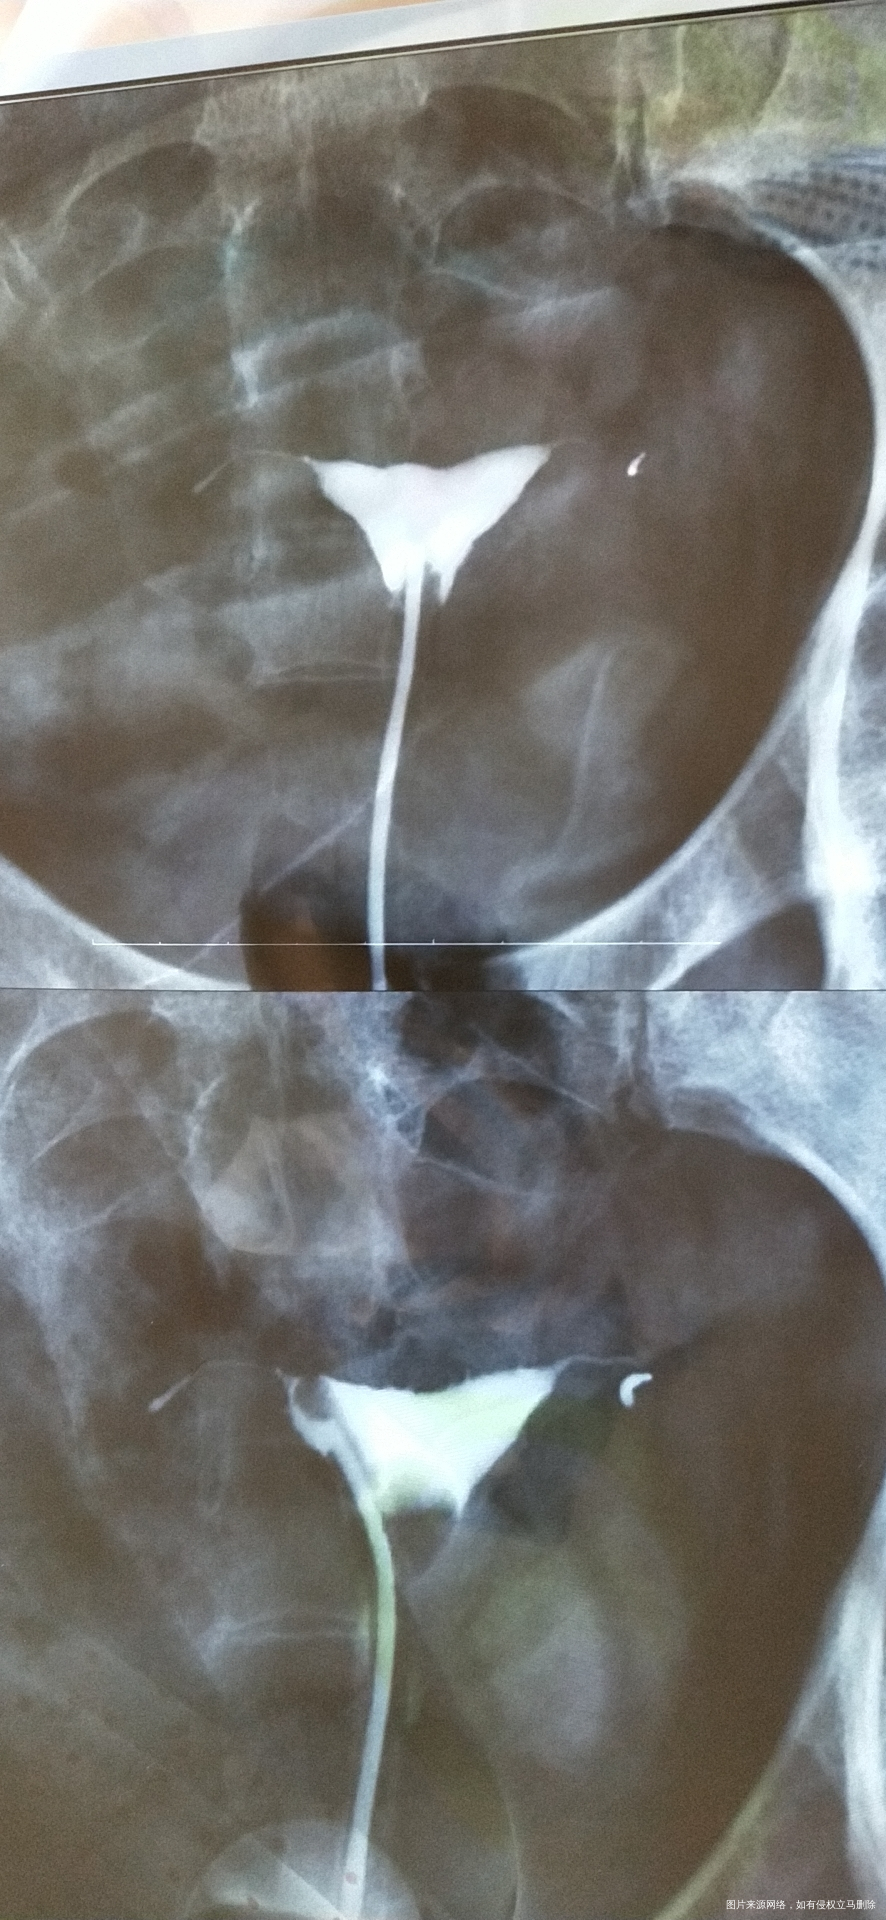

最下面的报告根本看不清,单纯输卵管堵塞不是大问题,我觉得更主要的是你高龄因素,可能导致卵巢储备功能低下,卵子质量差,这才是难处理的,先去检查基础性激素和窦卵泡数还有AMH,评估下卵巢储备功能,你的输卵管情况不是问题,大不了直接试管助孕,先去看卵巢储备功能!

目前造影看自然受孕几率不大 你年龄偏大 如果有迫切的生育要求建议尽快试管

41岁(高龄),+右侧输卵管堵塞,左侧输卵管缺如。建议直接试管。具体可以到当地生殖中心详细评估一下夫妻双方情况后决定